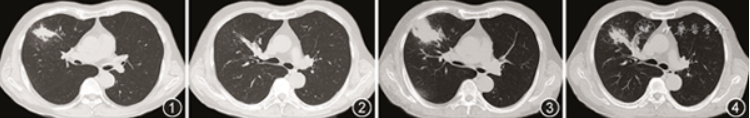

患者首先接受了2周的伏立康唑(200 mg,2次/d)口服治疗,但症状改善不明显,复查支气管镜仍可见嵌塞的黏液栓(给予活检钳反复钳夹黏液栓以通畅管腔,支气管腔内未见新生物)。综合以上,我们修正诊断为由Triodiomyces crassus引起的变应性支气管肺真菌病(allergic bronchopulmonary mycosis,ABPM),加用了口服糖皮质激素治疗(泼尼松20 mg,1次/d)。15 d后患者来电诉咳出一绿豆大小的胶冻状物质(黏液栓),咳嗽及胸闷有明显改善。此后患者继续服用了15 d的泼尼松,因惧怕激素不良反应及CT辐射患者自行停用泼尼松,并未按时复查CT。伏立康唑的总使用疗程近2个月。距首次入院77 d时患者复诊(已停药约15 d),临床症状缓解,复测血嗜酸粒细胞计数及总IgE已正常(表1),复查胸部CT病灶也明显吸收,遗留轻微的支气管扩张(图20)。考虑到患者已停用激素且症状未见反复,故继续停药观察。距首次入院6个月后,复查血常规及总IgE仍正常(表1),胸部CT仅遗留少许条索影,疾病未见复发。

图20 2018年7月31日胸部CT:原右上肺肺部阴影消失,遗留轻微支气管扩张